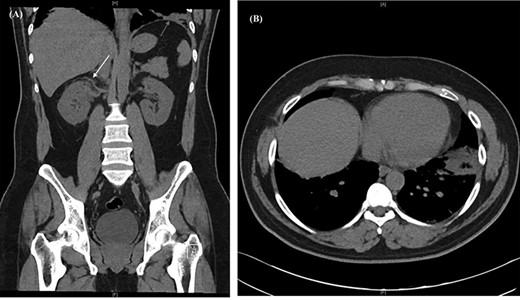

Chest radiograph demonstrated signs of left basal atelectasis, subsequently leading to the diagnosis of community-acquired pneumonia and discharge on oral antibiotics. Given the abdominal pain, other differential diagnoses included pulmonary embolism (PE) and renal colic. PE was excluded at initial presentation using the Pulmonary Embolism Rule-out Criteria (PERC) [4]. Blood work showed a leucocytosis and neutrophilia (Table 1). A computerized tomography urogram (CTU) obtained for suspicion of renal colic showed no renal tract obstruction, subtle right peri-nephric fat stranding and left lower lobe consolidation (Fig. 1).

CT urogram showing (A) right peri-nephric fat stranding (white arrow) with left lower lobe consolidation (red arrow) and (B) transverse section highlighting the left basal consolidation.